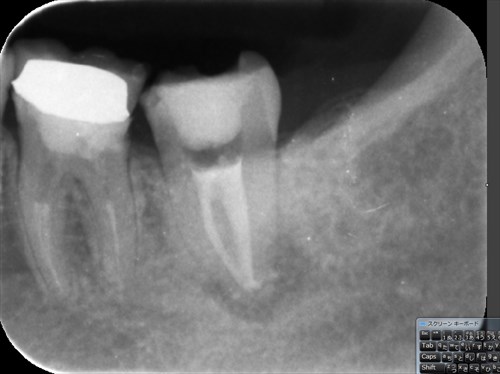

本日はエンド、ペリオ(重症のむし歯で神経が死に歯周病を併発した)患者さまの型とりの日でした。下記のように根の先に膿が出来てしまいそれが歯周ポケットと交通しています。ポケットは9mm。割れてはいないようでした。

CTでこのように精密に診断することにより的確な治療方法がお話でき納得されていました。